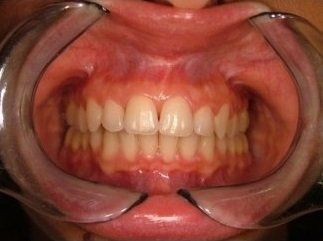

I risultati dell’ortodonzia linguale sono gli stessi di quelli ottenuti con gli apparecchi tradizionali, ma a causa della maggiore difficoltà che possono incontrare gli operatori questa tecnica è ancora usata solo da pochi specialisti in Italia e nel mondo.

Il trattamento ortodontico non rappresenta più una preoccupazione di inestetismo del sorriso durante il trattamento, ma anzi permette di apprezzarne gli avanzamenti sin dall’inizio. Il lieve imbarazzo fonetico dovuto all'interferenza dei brackets con la lingua viene superato in pochi giorni di adattamento, e solo in casi rari può richiedere fino a un mese.

I vantaggi dell’ortodonzia linguale vanno oltre l'invisibilità: consente infatti una maggiore velocità del trattamento, soprattutto nei casi con morso coperto, un minor rischio di retrazioni gengivali visibili. Garantisce un minor rischio di danni allo smalto dei denti nella superficie anteriore e una notevole efficacia nell'affrontare sintomatologie dovute a disordini e disfunzioni cranio-mandibolari.